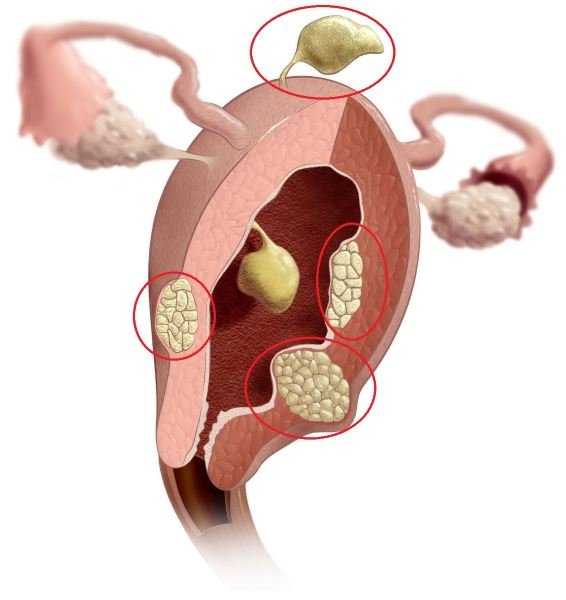

- аномалии строения матки. В норме орган имеет слизистую оболочку эндометрий и мышечный слой. Часто встречается орган неправильной формы — двурогая матка. Кроме того, в её стенке может располагаться доброкачественное новообразование из мышечного слоя — миома. В этом случае полость, где развивается эмбрион, имеет неправильную форму, что деформирует его оболочки и замедляет скорость роста плода;

Миома — доброкачественная опухоль из мышечных клеток среднего слоя матки